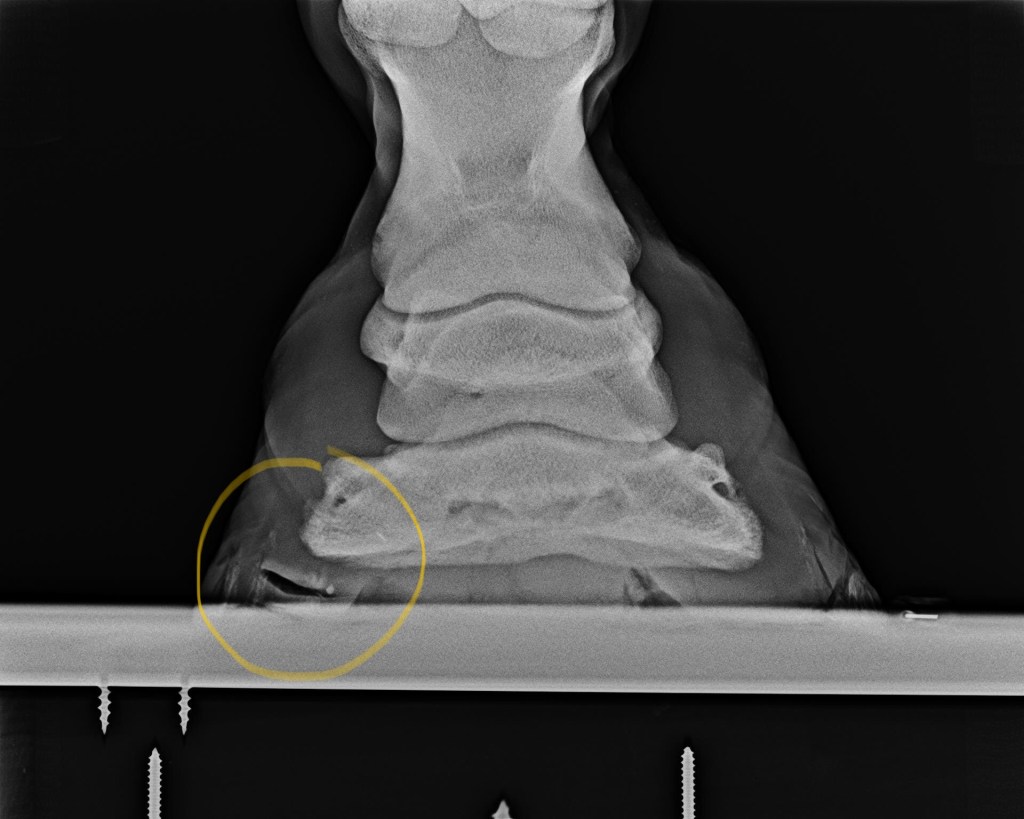

Image source: